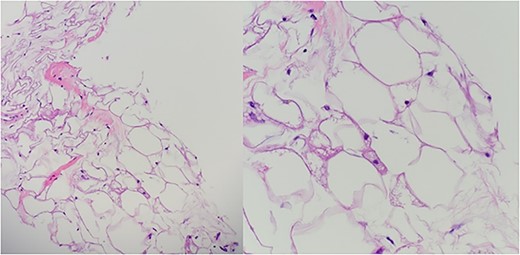

A 32-year-old female presented to the clinic with a palpable soft tissue back mass noticed a month prior to her visit. The patient had not noticed any change in size. On physical examination, a minimally mobile painless soft tissue mass was palpated and located on the left side of the back. No skin changes were noted. The mass was ~13 × 15 cm on palpation. No punctate, drainage nor erythema were noted. The mass was not attached to the skin. Ultrasound was performed 20 days prior to her visit and detailed a large soft tissue mass at the site of clinical concern in the patient’s back on the left side measuring 10.5 × 8.5 × 3.3 cm. Ultrasound-guided core biopsy was performed under local anesthetic in the office setting and demonstrated a Lobulated tumor composed of a mixture of cell types in varying proportions with small, bland, central nuclei, polygonal cells with granular eosinophilic cytoplasm and multivacuolated cells with numerous lipid droplets. Some univacuolated adipocytes were identified. Medium-sized prominent stromal vessels were noticed. Mitotic figures were rare. A computed tomography (CT) scan of chest with contrast was performed to estimate the relationship of the mass to adjacent anatomical structures. The CT scan showed 12.6 × 10 × 3.9 cm lipomatous mass beneath the latissimus dorsi muscle along posterolateral aspect of upper abdomen/lower thorax favoring an intramuscular lipoma (Fig. 3). Patient agreed to have complete excision of the mass. After excision in the operating room, the specimen was sent to pathology and showed a well-circumscribed 266 gm fatty mass that was serially sectioned revealing homogenous yellow adipose tissue on cut section (Fig. 2). The specimen was submitted per grossing protocol which is one section per 1 cm. Final pathology confirmed diagnosis of hibernoma (Fig. 1).

In the emergency department, vital signs were remarkable for elevated blood pressure of 166/81, but otherwise stable and afebrile. WBC count was elevated at 15.4 with left shift and hemoglobin was low at 9.6. Complete Metabolic Panel was notable for hyponatremia of 128, and mildly elevated BUN/serum creatinine of 26/1.5 which was slightly higher than his baseline of 17/1.3. Liver function tests were unremarkable. UA showed likely UTI with positive esterase, high RBC/WBC and bacteria and protein. A CT of the abdomen and pelvis was done, showing a left non-obstructing kidney stone and a left retroperitoneal fat density with stranding along the left iliopsoas measuring 12.6 × 8.1 cm × 3.7 cm, which was described as possibly a part of infectious or malignant process (Fig. 5). Subsequently, patient’s prior CT scans were available to be reviewed and it showed the same lipomatous mass 9 years earlier. (Fig. 6). Given the patient’s symptoms of left lower extremity pain and the possibility that the mass was responsible, a CT-guided core biopsy was ordered for diagnosis to rule out a malignant process as operative intervention was being contemplated. Pathology report of the core biopsy showed lobules of univacuolated adipocytes divided by thin septa. There were frequent multivacuolated adipocytes with small round nuclei, reminiscent of brown fat cells. No enlarged hyperchromatic cells, mitotic figures nor necrosis are seen. The findings supported the diagnosis of the lipoma variant of hibernoma (Fig. 4). Given the chronicity of the mass, the near identical size over 9 years and the diagnosis made from core biopsy, it was determined that the hibernoma was not the likely source of the patient’s LLE pain and hence the mass was not excised.

The diagnostic criteria for hibernomas include a circumscribed, lobulated, grossly yellow-brown mass with cellular features of brown fat, including numerous small cytoplasmic vacuoles and eosinophilic granular cytoplasm [6, 9]. Hibernomas are polygonal cytologically bland cells with small and central nuclei, prominent nucleoli, with rare cytologic atypia and mitotic figures [6]. The conventional lipoma in contrast to hibernomas are tumors with differentiation toward white fat cells [12]. The lipoma-like hibernoma variant has copious amounts of univacuolated cells mixed with scattered few granular multivacuolated hibernoma brown fat-like cells [8].